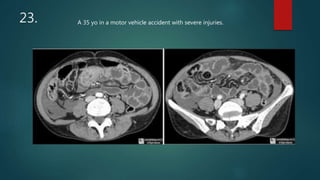

This document appears to be a medical report discussing several patients. It mentions a 35-year-old who was in a severe motor vehicle accident and an 81-year-old with a history of a non-vegetarian diet who had a perforated bowel from a chicken bone. The document provides few other details across its 25 numbered entries and was authored by Dr. Anish Choudhary for junior year 3 on May 30, 2016.